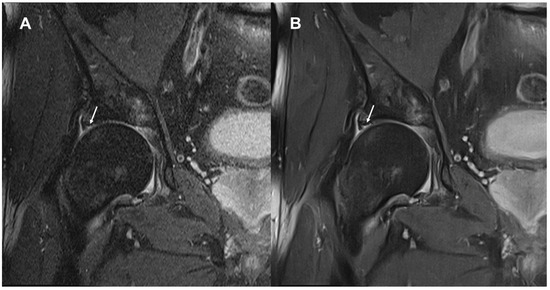

3.1. Image Quality

3.2. Delineation of Anatomic Structures and Internal Derangement